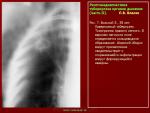

Происходит кавернизация туберкуломы в S2 верхней доли правого легкого

Толстые стенки образования, центральный характер распада, нежная дорожка к корню, я предположил бы периферический рак с распадом, да и возраст к этому располагает. Дифференцировать с туберкуломой, с распадом.

Думаю сначала следует исключить кавернозный тбс учитывая локализацию и фиброзные изменения. Хотя по характеру полости и стенок больше за рак действительно. Но тут нехватает выраженой лимфоаденопатии корня...В общем случай достаточно сложный для диф.диагностики по рентгену. По традиции на первое место поставлю рак с распадом. Обосную отсутствием изменений кл.ан. крови.

Присмотритесь к контуру внутренней поверхности, он волнистый, образован как бы наложением кругов разных диаметров. В интерпретации - несколько очагов образовали общую полость после распада. Не так ли вторичные формы туберкульоза получаются? (каверна в частности).